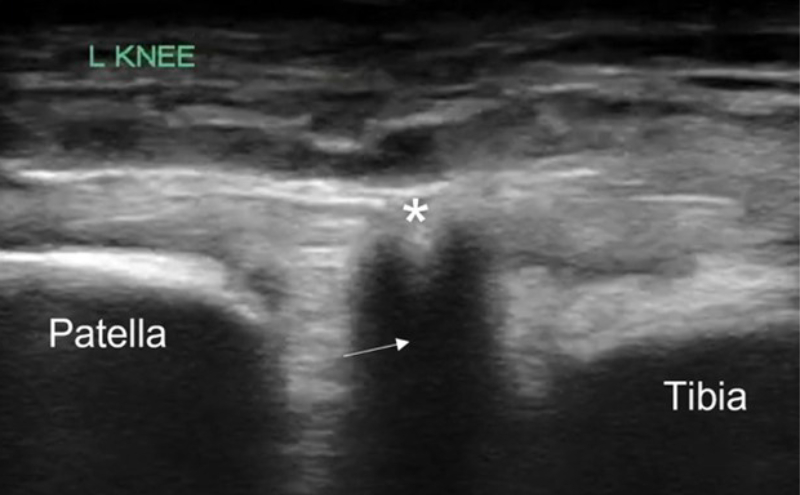

POCUS of the left knee was performed, which was concerning for a patellar tendon rupture and a joint effusion. (Figure 1 and Video 1) In addition, there was posterior acoustic shadowing obscuring part of the patellar tendon concerning for an avulsed bony fragment. (Figure 2) X-rays were performed, which confirmed the suspected diagnosis of a left tibial tubercle avulsion. (Figure 3) The patient was ultimately taken to the operating room for an Open Reduction and Internal Fixation (ORIF) by Orthopedic Surgery and discharged home the following day in a knee brace.

Figure 2. Patellar tendon with focus of acoustic shadowing (arrow) concerning for avulsed bony fragment (*)

In our case report, we successfully identified key features suggestive of tibial tubercle fractures: disruption of the patellar tendon, posterior acoustic shadowing of a bone fragment, and a large joint effusion. To perform knee ultrasound, the linear probe should be used and placed inferior to the patella in sagittal plane. The patellar tendon should be visualized in two planes, fanning through it completely (Video 1), and compared to the contralateral normal knee. (Figure 4) Abnormal findings suggestive of epiphyseal fractures include disruption of the tendon, an increased hypoechoic space adjacent to or posterior to the tendon (suggestive of either hemarthrosis or a hematoma), or a hypoechoic zone (ie, posterior acoustic shadowing due to an avulsed bony fragment).3,4